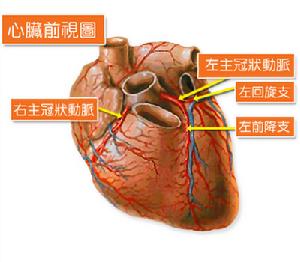

1.節段性或瀰漫性心肌損害節段性心肌損害如心肌梗塞,心肌缺血。瀰漫性心肌損害如心肌炎、擴張型心肌病、肥厚型和限制型心肌病以及結締組織疾病的心肌損害等。

1.壓力負荷過重見於高血壓,主動脈瓣狹窄;肺動脈高壓,肺動脈瓣狹窄等左、右心室收縮期射血阻抗增高的情況。

心衰 1、心肌衰竭 冠心病、急性心肌梗死、室壁瘤瀰漫性心肌炎(風濕性、病毒性、中毒性感染性)、克山病、擴張型心肌病圍產期心肌病。酒精中毒性心肌病、甲狀腺機能減退症肢端肥大症、皮質醇增多症、心肌澱粉樣變性結節病、血色病、糖原積累症糖尿病、尿毒症、系統性紅斑狼瘡硬皮病、皮肌炎、多發性動脈炎類風濕性關節炎、強直性脊柱炎、多發性肌炎進行性肌營養不良、萎縮性肌強直、遺傳性共濟失調盪多糖病工型、轉移性心臟腫瘤、白血病左心發育不全綜合徵、過度肥厚、老年性心臟改變放射性、藥物性、毒物貧血性心臟病、急性或慢性肺源性心臟病、高山病甲狀腺功能亢進、維生素Bl缺乏病。

2、後負荷過度 主動脈瓣狹窄、三尖瓣關閉不全、厚性梗阻型心肌病胸厚型主動脈瓣下狹窄原發性高血壓、腎性高血壓、主動脈瓣狹窄肺動脈瓣狹窄、三尖瓣關閉不全、肥厚型梗阻性心肌病肥厚型主動脈瓣下狹窄、原發性高血壓、腎性高血壓主動脈縮窄、原發性肺動脈高血壓、Barnheim綜合徵妊娠毒血症、艾森曼格綜合徵。

1、左心衰竭 冠心病、高血壓、主動脈瓣狹窄主動脈瓣關閉不全肥厚性梗阻型心肌病、二尖瓣關閉不全、急性腎小球腎炎急性腎衰竭、輸血輸液過多過速。

2、右心衰竭 急性肺動脈栓塞、慢性肺源性心臟病、先天性肺動脈瓣狹窄缺損較大的房間隔缺損和動脈導管未閉伴有大量左至右分流並發肺動脈高壓者、限制型心肌病、縮窄性心包炎右心室阻塞性衰竭綜合徵、原發性肺動脈高壓症。

心電圖 九、急性心肌梗死與心肌硬化

急性心肌梗死並發泵衰竭時可並發心源性休克與急性左心衰竭重者可發生肺水腫。心衰通常在發病最初幾天內,或在疼痛休克好轉階段出現,呼吸困難、發組嚴重時可發生肺水腫。患者多為中老年男性,常有高血壓、高脂血症、糖尿病、肥胖吸菸等易患因素。患者主要表現為胸骨後或心前區持續時間較長而劇烈的疼痛,並向左肩或左上肢內側放射或伴有噁心、嘔吐、出汗等心率增快,心律失常,心音低鈍可出現房性或室性奔馬律,少數有心包摩擦音,若並發室間隔穿孔或乳頭肌斷裂可突然出現響亮的收縮期雜音。如急性心肌梗死面積較大,心肌壞死超過左心室總面積40%-60%時可發生心源性休克、血壓下降、煩躁不安面色蒼白、皮膚濕冷、大汗脈細弱、尿量減少等休克表現。心電圖示有盯段抬高病理性Q波及 T波倒置或高聳。心電向量示 T向量和 QRS向量背離梗死區,盯向量指向梗死區當左束支傳導阻滯時,心肌梗死的心電圖改變可被掩蓋。實驗室檢查穀草氨基轉移酶(SGOT)肌酸磷酸激酶(CPK)和乳酸脫氫酶(LDH)及同工酶LDH1升高,LDH1>1。血和尿肌紅蛋白在梗死後2-4h開始升高且恢復較慢。放射性核素99鎝和20 鉈掃描或照相均可顯示梗死的部位和範圍。

心肌硬化系由於長期心肌缺血營養障礙,心肌萎縮;或大片多次小灶性心肌梗死後,瘢痕形成心肌細胞減少,纖維結締組織增多。主要臨床特點為: